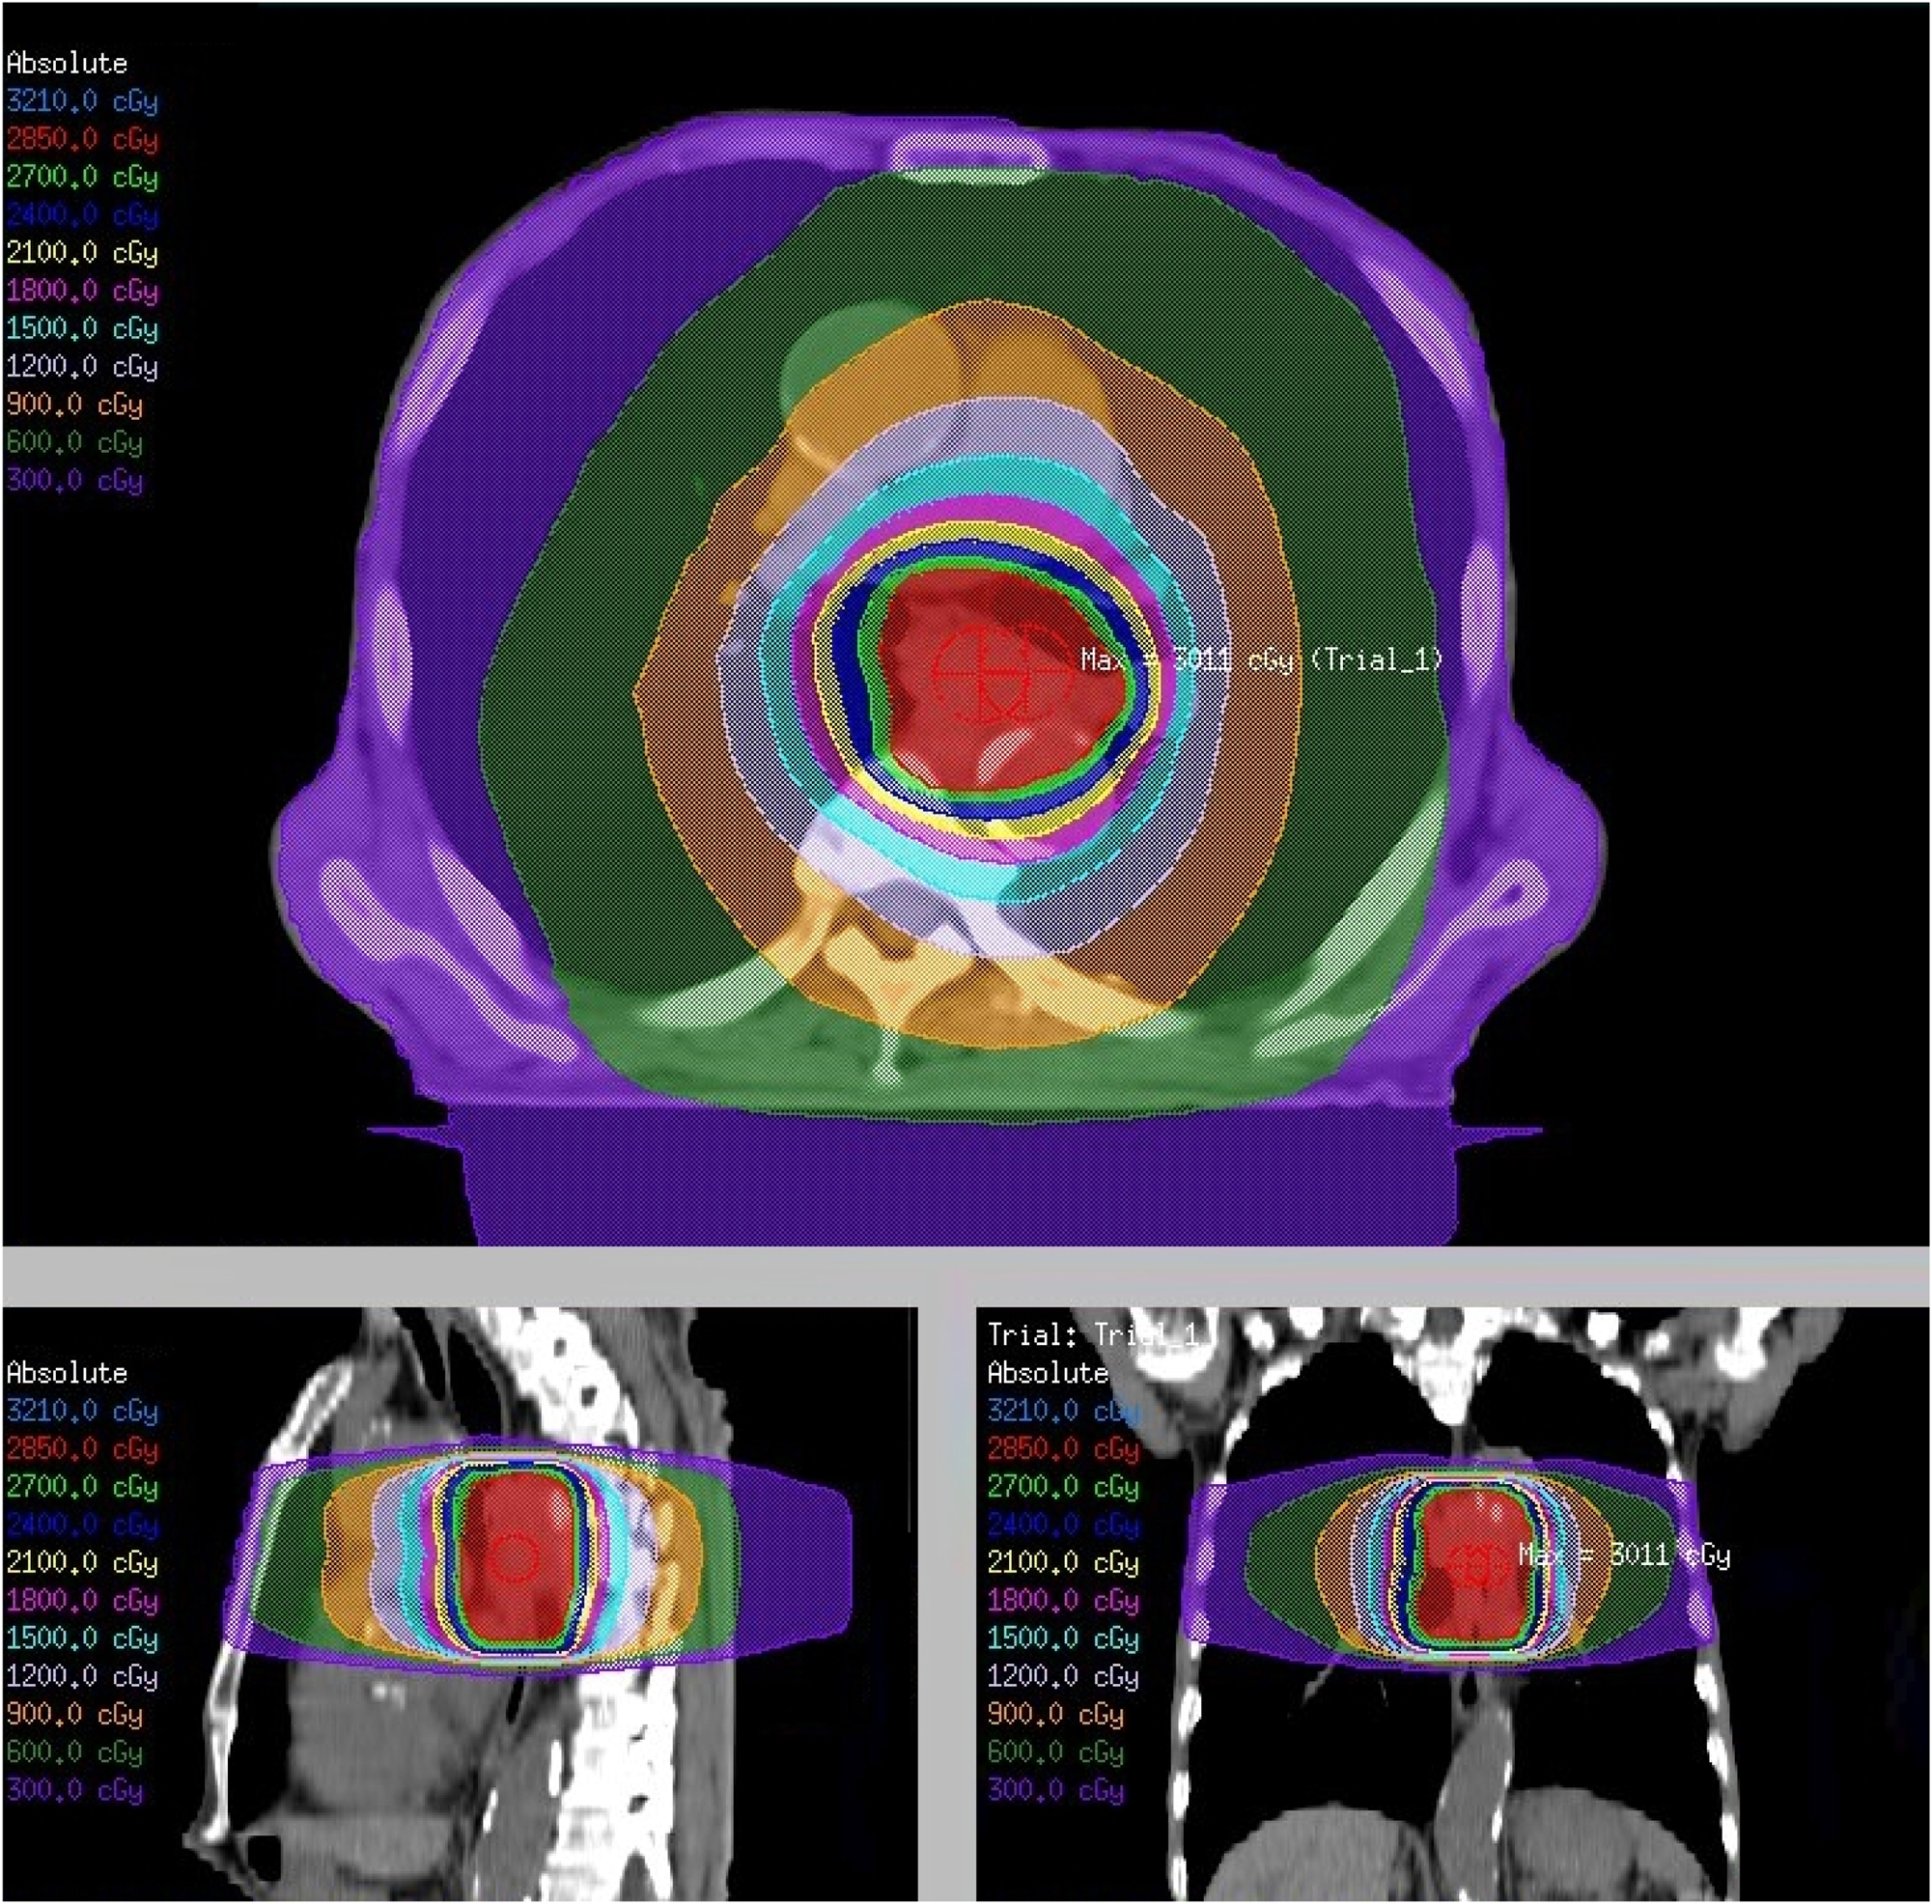

Several palliative interventions are available for managing dysphagia, including self-expanding metal stents (SEMS), external beam radiotherapy (EBRT), brachytherapy, and chemoradiotherapy [5], 6]. SEMS provide rapid relief from dysphagia but are associated with frequent complications and the need for repeated interventions [7]. Brachytherapy offers sustained symptom control but is less commonly used owing to its invasive nature and limited accessibility [8]. EBRT has become a widely used alternative, offering effective relief from gastrointestinal cancer symptoms with fewer complications [9], [10], [11]. The target field for palliative radiotherapy for dysphagia in esophageal cancer typically includes the radiological tumor volume with limited margins accounting for respiratory motion and setup errors without elective nodal irradiation (Figure 1). This review aims to clearly define the clinical role of EBRT as a palliative treatment option for dysphagia in patients with advanced esophageal cancer. This evaluates the effectiveness and characteristics of EBRT in comparison with other palliative modalities, explores the potential of combination therapies and novel radiation schedules, and discusses future strategies to enhance the quality of patient care.

Figure 1:

Palliative external beam radiotherapy for dysphagia in advanced esophageal cancer. A radiation dose distribution plan for a prescription dose of 30 Gy in 10 fractions. The top image represents an axial cross-section, the bottom left image represents a sagittal section, and the bottom right image represents a coronal section. The color-coded isodose lines indicate different radiation dose levels measured in centigray (cGy). The maximum dose is noted as “Max: 3011 cGy”. This figure is based on the institutional data and treatment planning system and has not been published elsewhere.